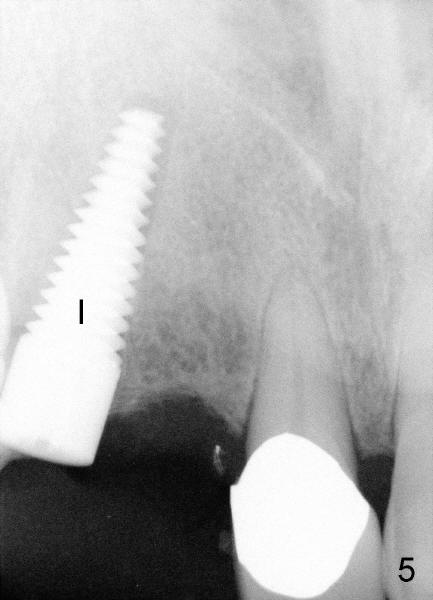

Immediately after atraumatic extraction of #6 residual root, the socket is irrigated with normal saline and Chlorhexidine. There is no granulation tissue in the apical area. The root stump is 6 mm mesiodistally and 8.5 mm labiopalatally. Tatum 2 mm pilot drill is used with copious irrigation to penetrate the palatal plate of the socket (as shown by arrow in Fig.2) at the depth of 20 mm from gingival margin. Bicon reamers (cylindrical, from 2.5 mm to 4.0 mm in a sequential order) are used (with 400:1 reduction) for osteotomy without irrigation. Autogenous bone graft is collected to fill the gap between implant and socket. Fig.4 shows 3.0 mm reamer in place (20 mm from the gingival margin). Finally Tatum tapered implant 6x20 mm is torqued in with primary stability (Fig.5: I). There is no gap between the implant and the socket except palatally, where the bone graft is inserted. Two release incisions are placed palatally. The flap is raised. The periosteum is scored at the base. The palatal flap is advanced labially to close the palatal gap with 4-0 chromic gut suture.

There is approximately 8 mm between the tooth #8 and the implant at the site of #6 (Fig.6,7). The distance appears to be enough to place D2 and D1 implants (Fig.6,7, respectively).